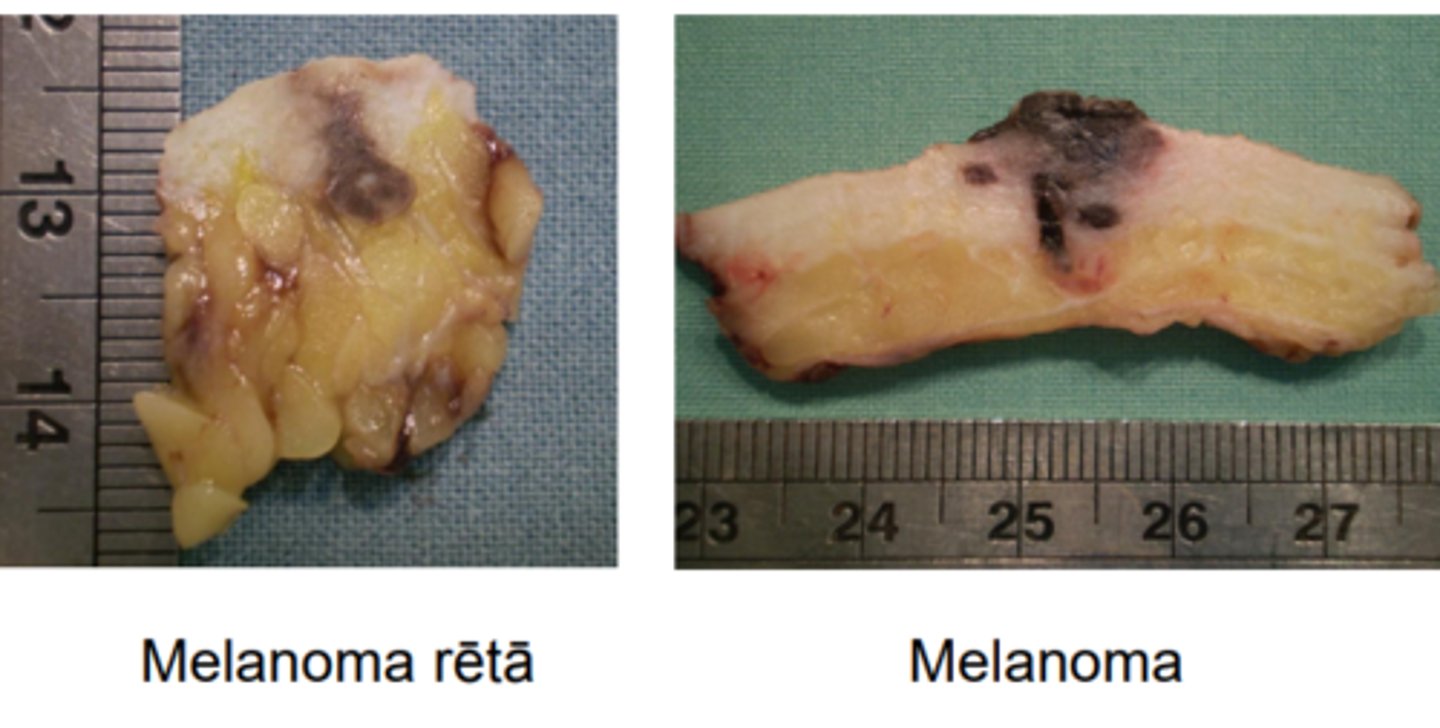

Melanoma pic

5

New cards

Melanoma: izteikta šūnu atipija un melanīna sintēze